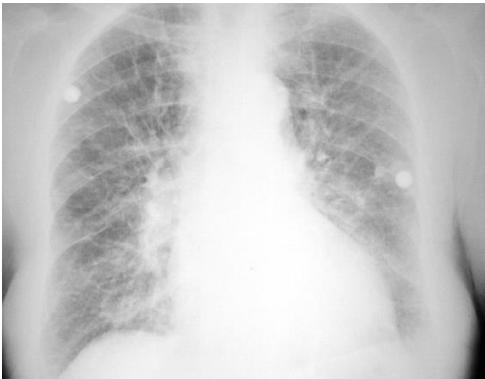

Pulmonary Edema

- Diagnosis: Pulmonary Edema.

- Radiological Signs:

- Cephalization (early).

- Kerley B lines, peribronchial cuffing.

- Bat wing or butterfly appearance (late/severe).

- Cardiomegaly.

- Differential Diagnosis: Pneumonia, ARDS.

- Management:

- Position: Sitting up.

- Respiratory support (CPAP or BiPAP).

- Diuretics (Furosemide), Vasodilators (Nitroglycerin).